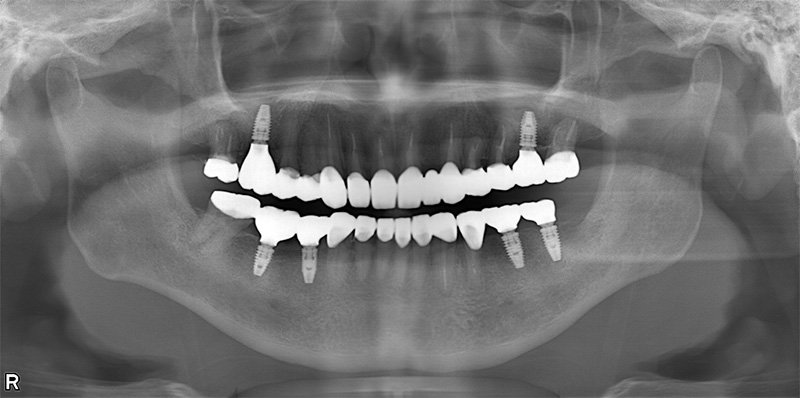

57歳男性

治療前

治療後

| 施術名 | インプラント治療 |

| 施術の説明 | インプラント治療とは、歯を抜いた所にチタン製の人工歯根を埋入し、新しく歯を入れる方法です。 |

| 施術の副作用 (リスク) | 腫れや疼痛を感じる、違和感を感じるなどの症状を生じることがあります。 |

| 施術の価格 | 53万円~+消費税 |